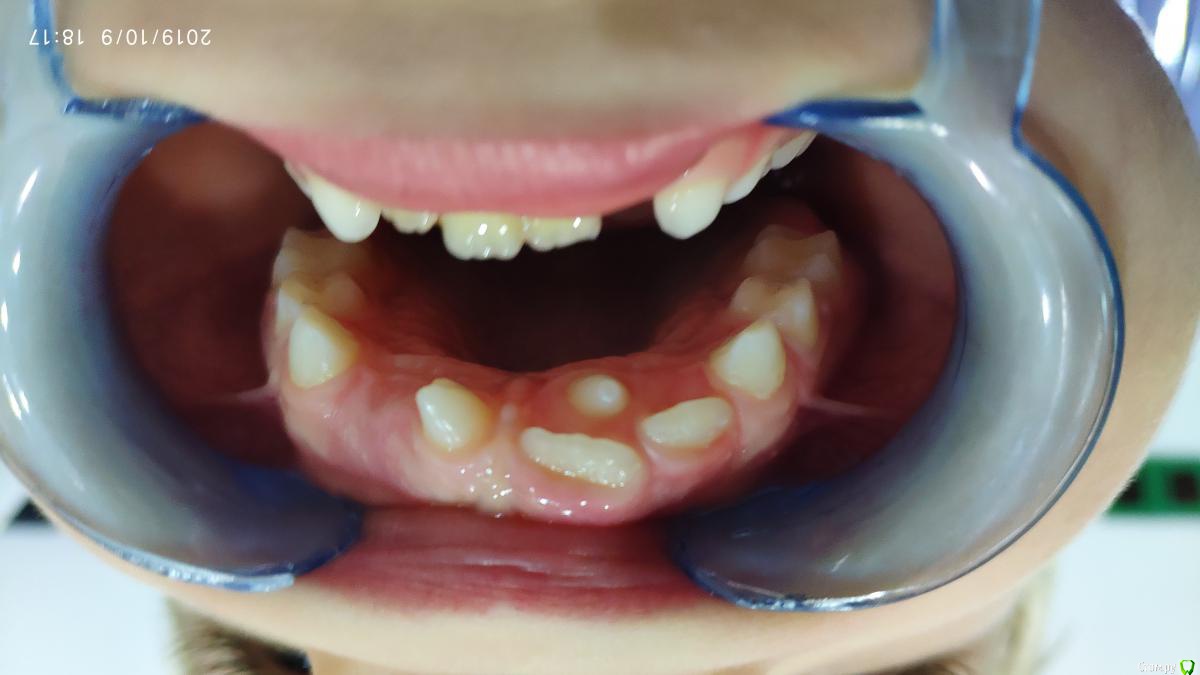

dr.i Опубликовано 11 октября, 2019 Поделиться Опубликовано 11 октября, 2019 (изменено) Нужна помощь в определении как быть в этой ситуации мне кажется здесь сверхкомплектные зубы,и скорее на удаление пойдут эти два зуба.что можете сказать по этому поводу. Изменено 11 октября, 2019 пользователем dr.i Ссылка на комментарий

сирена Опубликовано 11 октября, 2019 Поделиться Опубликовано 11 октября, 2019 Вам правильно кажется Ссылка на комментарий

sn3zhna Опубликовано 8 января, 2020 Поделиться Опубликовано 8 января, 2020 Все верно говорите. Ссылка на комментарий